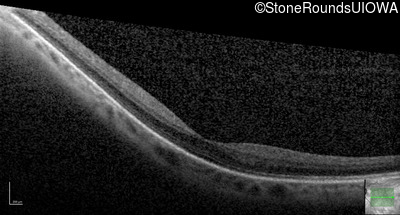

Optical Coherence Tomography - Left - 20/30 +1

Exemplar / OCT Stack